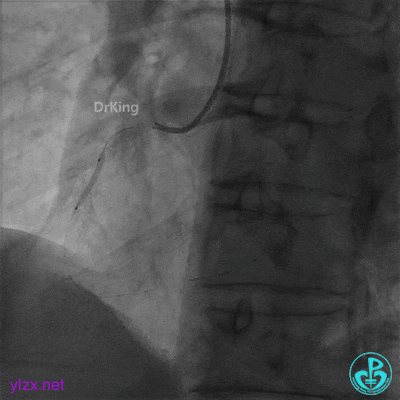

2.0×20mm球囊预扩张。

3.0×15mm双导丝球囊再次扩张。

双导丝球囊扩张后造影,血流缓慢,随即心率减慢至50次/分,血压降低至80/50mmHg,并出现短阵室速,随后意识丧失。